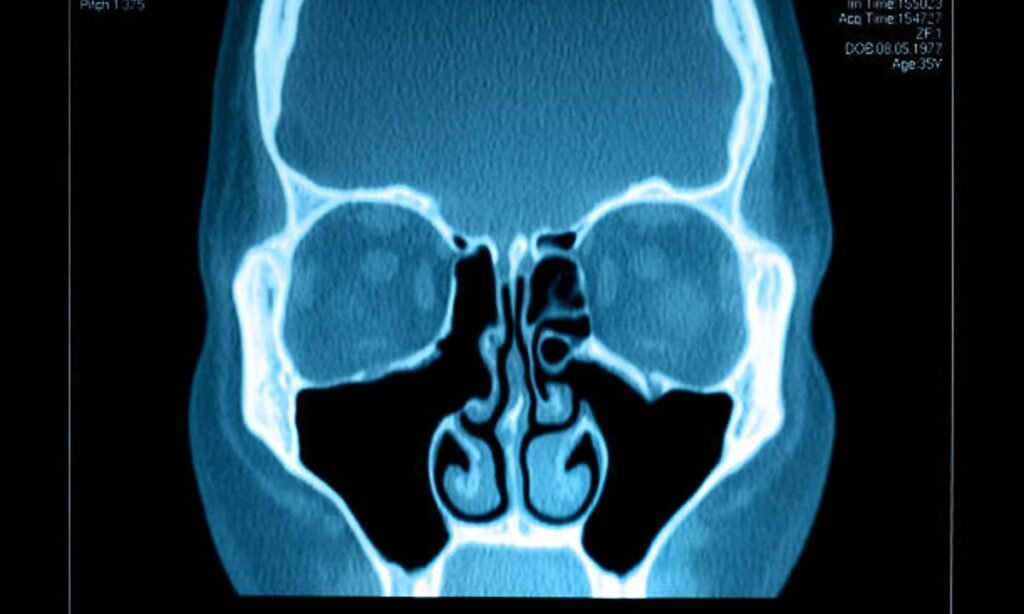

Understanding Sinus CT Scan: Process, Benefits, and More

A Sinus CT Scan remains among the standard medical procedures for obtaining comprehensive sinus images throughout the facial structures. The medical technique enables proper diagnosis of infection-related issues alongside inflammation conditions and blockages along with structural abnormalities in the sinuses. This article will explain key aspects of Sinus CT Scans by explaining their functioning process […]